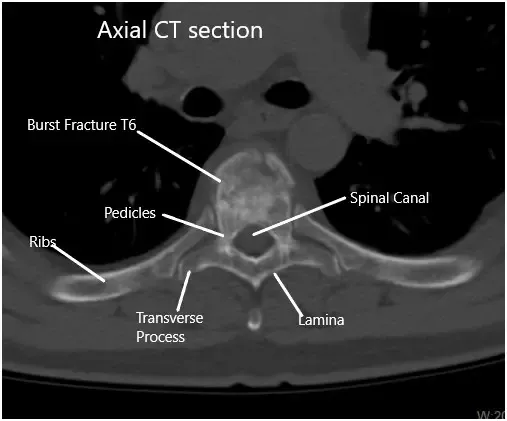

TAC preoperatorio de la columna toracolumbar en sección axial en T6

La TC reveló fractura aguda moderada por compresión de cuña asociada al cuerpo vertebral T6. La corteza posterior del cuerpo vertebral T6 se imprime ligeramente sobre el margen anterior del saco dural torácico. El hematoma mínimo se sitúa entre el cuerpo vertebral T6 y la pleura circundante.

Había una configuración normal de los cuerpos vertebrales torácicos restantes. Los espacios del disco torácico no están estrechados. No se demuestran protrufacciones discales posteriores ni hernias. El estrechamiento no está asociado con los forámenes neurales torácicos.